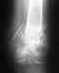

Дорогие коллеги! Я врач-хирург из г. Севастполя. Мне 34 года. 22.03.2012г. получил бытовую травму- упал с велосипеда. Получил сочетанную травму. Главная проблема перелом левой плечевой кости.

Как всегда у медиков все через ж... Мнения врачей разошлись. Открытая операция с МОС- высокий риск асептического некроза головки плечевой кости. Без операции- нарушение функции. Вы можете меня понять, что это значит для хирурга.Прошу Вас дать совет по дальнейшей тактике. Заранее благодарен.

• Кликните для загрузки файла DSC00156.JPG